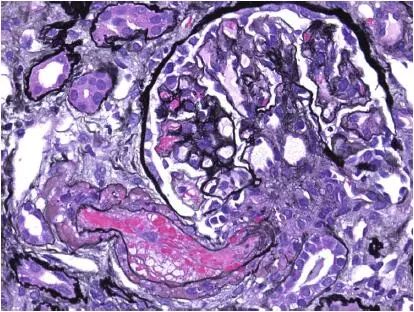

图1 CNI肾毒性TMA,小动脉(Jones 银染)

CNI肾毒性导致的血管收缩无形态学变化。急性CNI肾毒性特征包括:近端肾小管上皮细胞空泡化,大小一致;血管损伤,平滑肌细胞丢失;肌细胞胞浆空泡化;细胞坏死或凋亡退化。肌细胞损伤最终发展为局灶性结节性玻璃样变和透明样变,可延伸至小动脉和动脉血管壁整个中层。CNI肾毒性还可引起血栓性微血管病变(TMA),主要累及小动脉和肾小球毛细血管袢。慢性CNI毒性特征为:条状间质纤维化,肾小管萎缩。

近端肾小管上皮细胞空泡化,大小相等,内质网扩张,大型溶酶体。动脉中层和外膜透明质酸积聚。TMA患者可出现肾小球内皮细胞肿胀,内层扩张和肾小球系膜溶解。